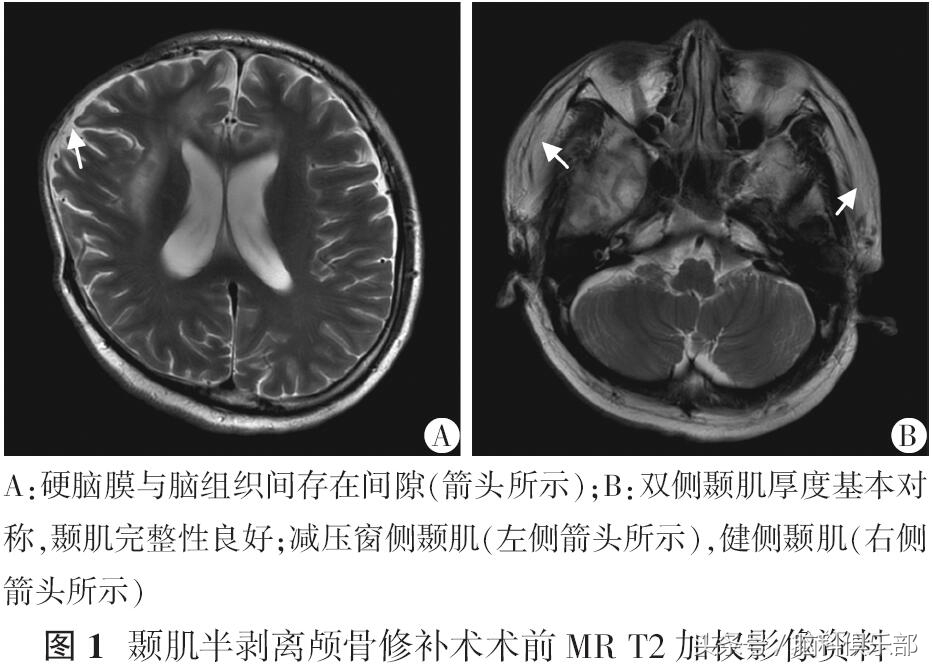

男性,41岁,3个月前行右侧额颞去骨瓣减压术,手术记录提示人工硬脑膜减张并水密封修补硬脑膜;患者头颅MR提示新生成硬脑膜与脑组织间存在间隙(图1A);颞肌组织厚度与对侧比较基本相同,临床查体颅骨缺损侧颞肌厚度可(图1B);术前患者减压窗无凹陷,并高于骨窗面。